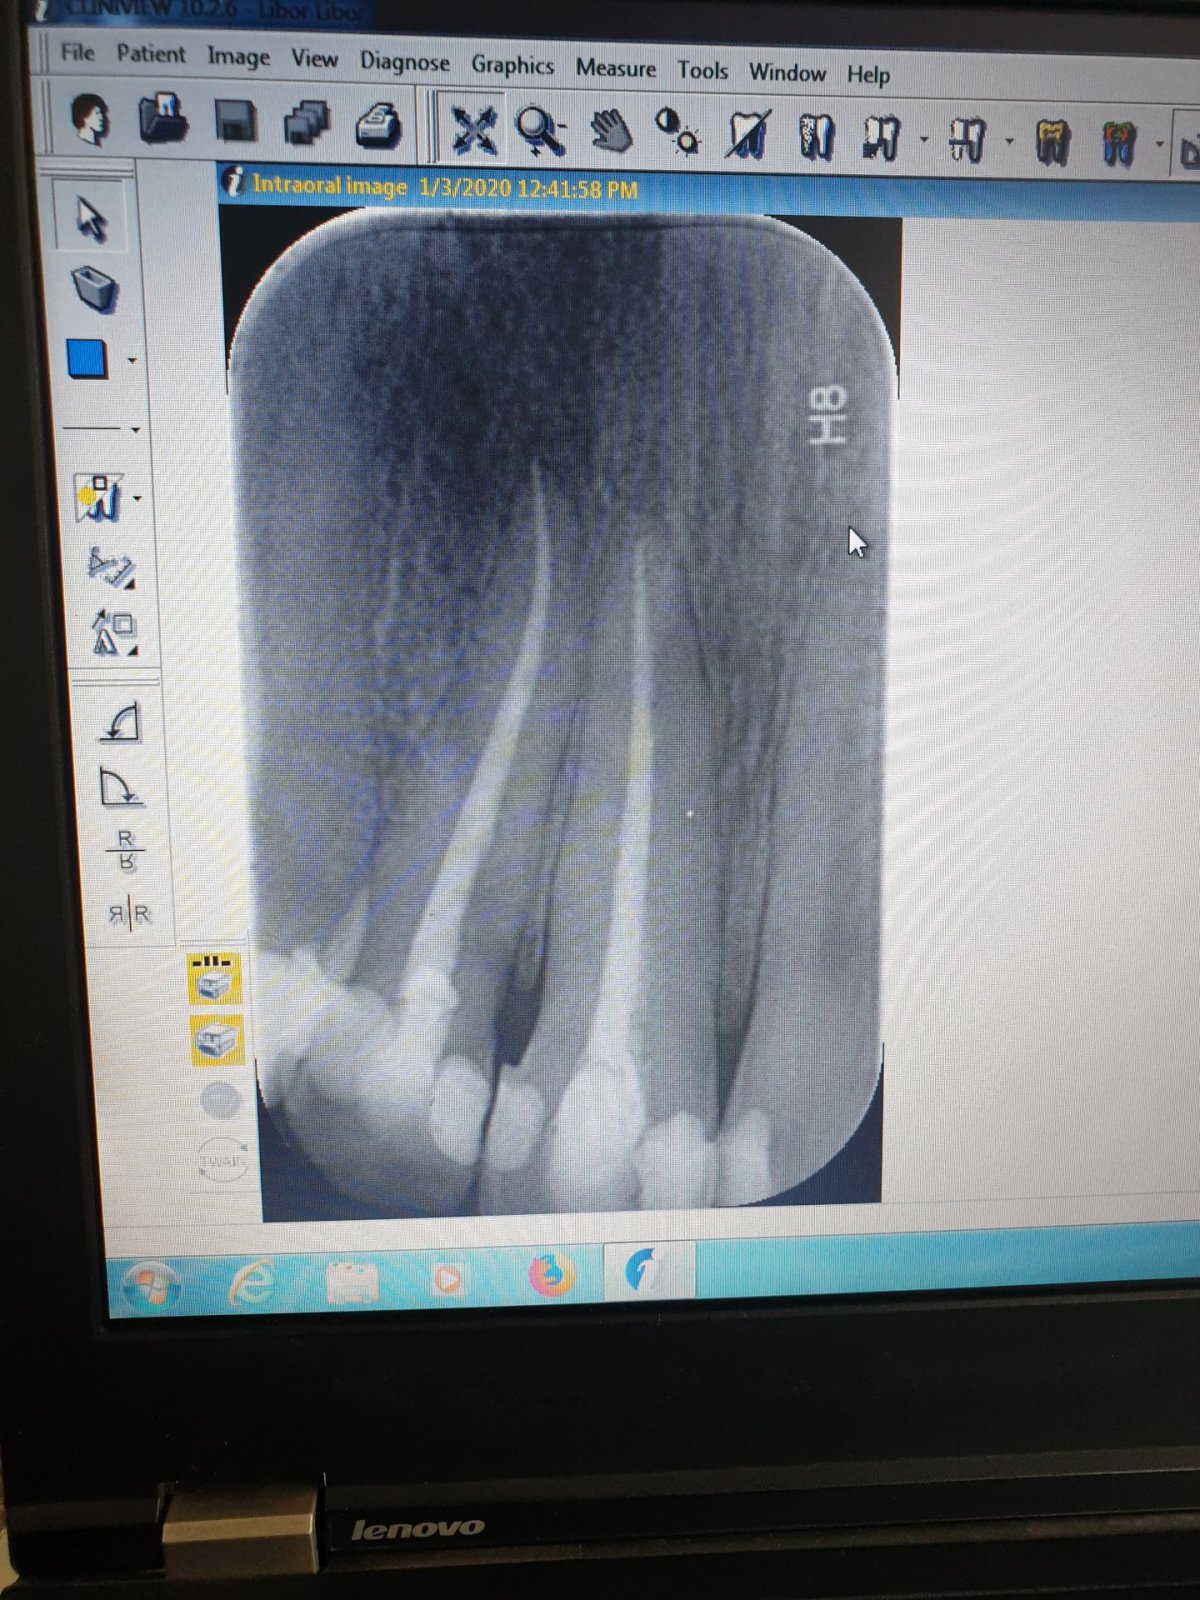

Na rentgenovém snímku mi ukázal, že po odstranění kazu nedošlo k úplnému vyplnění dutiny a kaz se znovu začal šířit. I přes trošku neortodoxní praktiky, jako třeba ponechání zubu otevřeného dva dny, které jsem konzultoval vzdáleně se svým známým, jenž má soukromou dentální ordinaci v Praze a za smějícími se smajlíky byly dobře rozpoznatelné jeho protáčející se oči, jsem byl po třech návštěvách, rozložených do jednoho týdne, spokojený. Zubařovo vychvalování svého umu, který si v ničem nezadá s evropskými kolegy, i mírný nátlak na "pět hvězdiček" v recenzi jeho kliniky bych mu klidně odpustil.

Rentgenové snímky jasně ukázaly chybně provednou výplň horního řezáku a další kaz na spodní stoličce